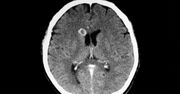

Boją się, że nikt nie uwierzy w to, co widzą i zostaną wysłani prosto do psychiatry. Dlatego często rezygnują z wizyty u lekarza, chociaż w rzeczywistości nie mają zaburzeń psychicznych. Przyczyna ich problemu może być jednak równie poważna: guz mózgu, udar, zapalenie mózgu czy borelioza. - Widziałam wodospady i motyle, a twarz mojego chłopaka zaczęła się wykrzywiać, stawała się wręcz wynaturzona. To były wizje jak z horroru - przyznaje Alicja, która zmaga się z Syndromem Alicji w Krainie Czarów.